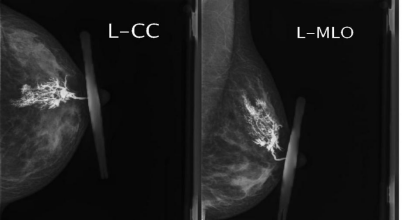

影像检查:乳腺彩超、乳腺X线、核磁共振。

乳腺X线(钼靶):40岁以上女性推荐,40岁以下女性医生根据具体情况选择。